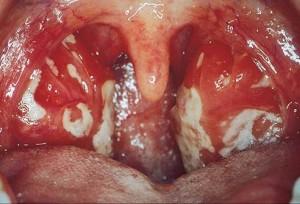

Las molestias en la faringe se acompañan a menudo por faringitis moderada o intensa, con agrandamiento marcado de las amígdalas y a veces con exudados.

Se suelen observar petequias en la unión de las porciones dura y blanda del paladar. La faringitis recuerda a la propia de una infección estreptocócica.